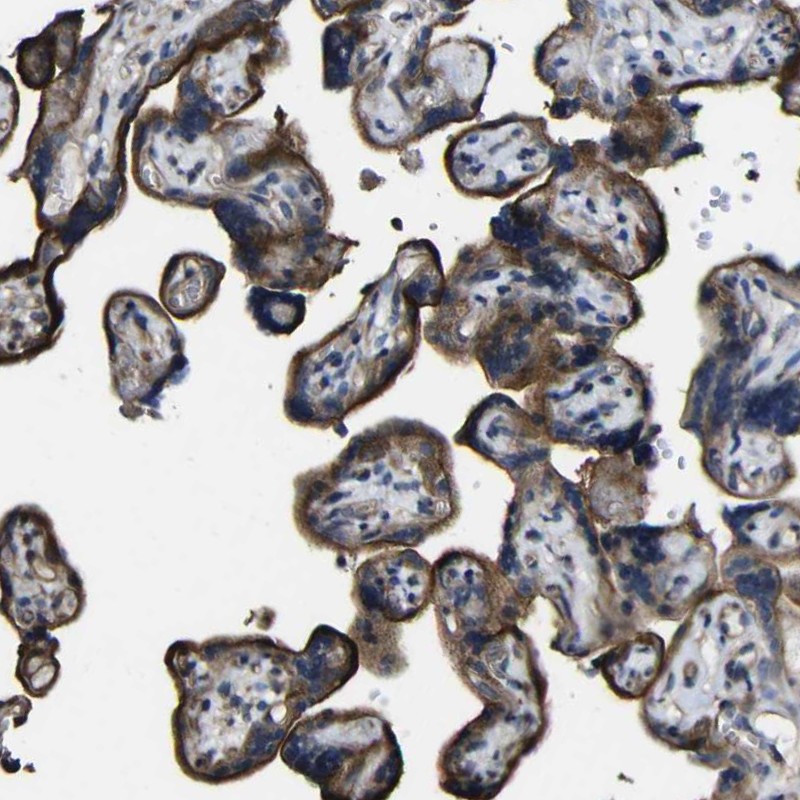

Immunohistochemical staining of human placenta shows strong membranous positivity in trophoblastic cells.